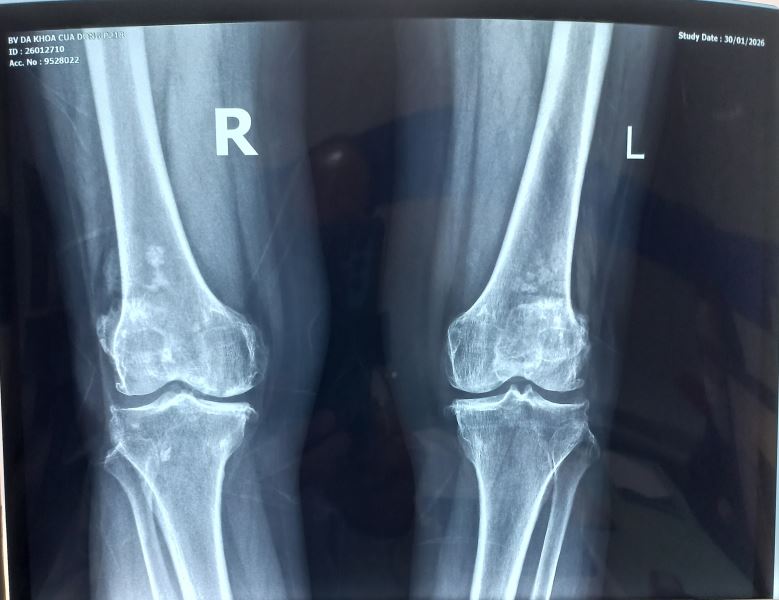

Chụp X-quang cho hình ảnh dưới đây.

Chúng tôi nghĩ đến bệnh Synovial Osteochondromatosis một loại bệnh hiếm gặp và cho bệnh chân chụp MRI khớp cho kết quả sau: